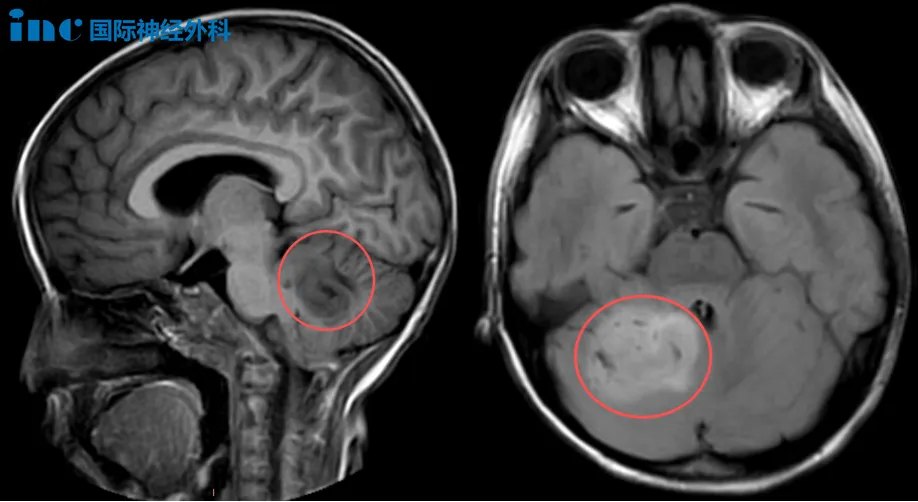

在巴教授主刀下,中國神經(jīng)外科專家團隊同臺合作,為一名腦膜瘤患者林先生實施了高難度的顯微神經(jīng)外科手術。

術前MRI

這臺手術的挑戰(zhàn)不僅在于腫瘤本身的復雜性,還源于患者曲折的治療過程。在長達12年的漫長抗爭中,林先生經(jīng)歷了一次開顱手術,兩次伽馬刀治療以及中藥治療……然而首次術后出現(xiàn)面癱,甚至右側耳朵里長出奇怪“腫瘤”,切除后不幸失聰,這一切無疑是對其身心的嚴峻考驗。然而這個狡猾的腫瘤依然不依不饒,瘋狂生長,侵犯多個區(qū)域,甚至已經(jīng)把三叉神經(jīng)和滑車神經(jīng)360°無死角的包裹。